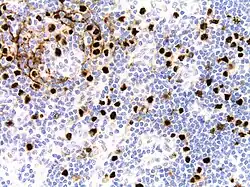

| Micrograph of HHV8-associated Castleman's Disease showing LANA-1 positive lymphoblasts in a regressed germinal center and mantle zone. LANA-1 stain. | |

Formal criteria for the diagnosis of HHV-8-associated MCD have not been published; however, diagnosis requires enlargement of lymph nodes in multiple lymph node regions (typically confirmed with radiologic imaging), histologic changes consistent with HHV-8-associated MCD on biopsy of an enlarged lymph node, and confirmation of HHV-8 infection by LANA-1 lymph node staining or peripheral blood polymerase chain reaction for HHV-8.[6] HIV testing is useful for management, but a positive result is not necessary for to diagnose HHV-8-associated MCD.[2]

Staining with latency-associated nuclear antigen (LANA-1), a marker for HHV-8 infection, is typically positive.[11]